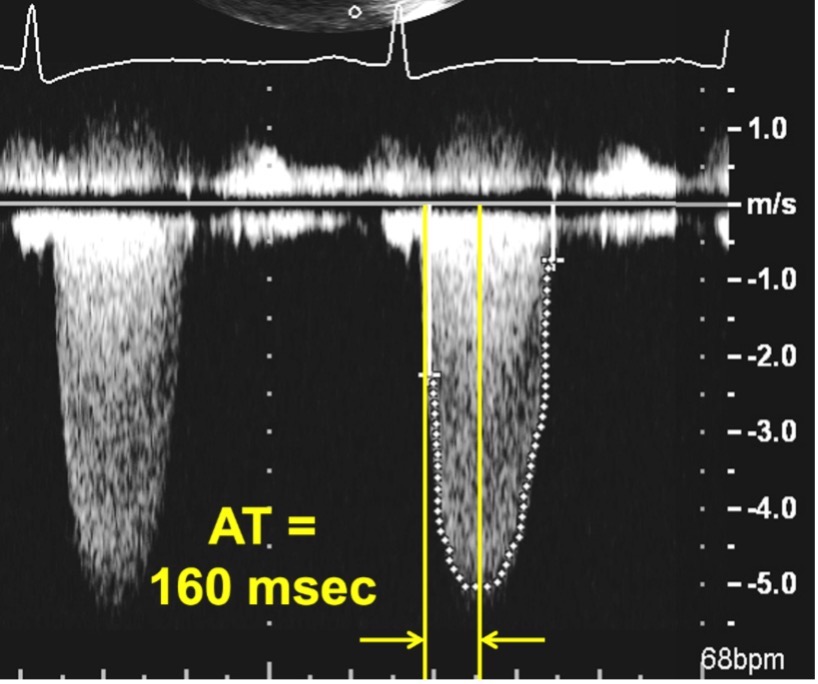

Fig. 9.A mitral pressure half time of